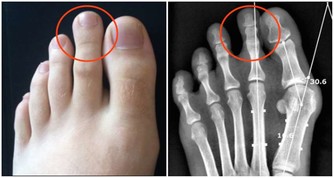

其中骨關節炎和類風濕關節炎這兩種是比較常見的,來看看二者的區別

骨關節炎:軟骨磨損

類風濕關節炎:滑膜病變

骨關節炎:僵硬、疼痛、不能握拳、大拇指不靈活、有硬結

類風濕關節炎:晨起後嚴重,活動後好轉

骨關節炎:X線檢查

類風濕關節炎:風濕4項、X線檢查

由此可見,雖然它們的症狀很像,但還是有區別的,希望大家不要混淆,自己亂貼藥膏可能並不能發揮作用。